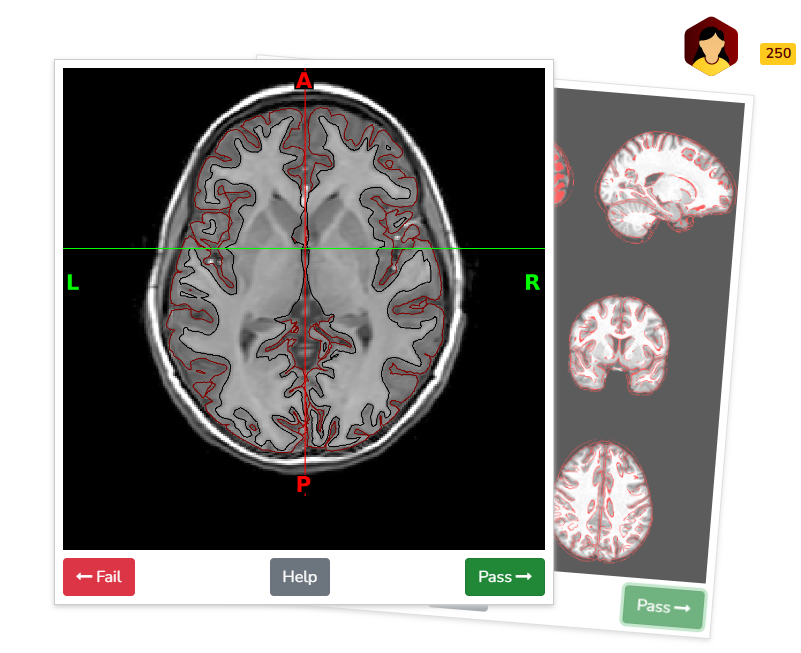

Manual visual inspection remains the gold standard for identifying artifacts in structural and functional derivatives (e.g., from the abcd-hcp-bids pipeline) and diffusion derivatives (e.g., from QSIPrep). To streamline this process, derivative visual reports are integrated into BrainSwipes, a gamified, crowdsourced QC platform built on the open-source Swipes For Science framework. BrainSwipes engages users in evaluating brain image quality through an intuitive interface designed for large-scale studies. After creating an account, users are guided through a brief tutorial that teaches them how to assess derivative images and classify them as pass or fail.

For structural QA, swipers are presented with image slices in coronal, axial, and sagittal planes to assess the accuracy of T1w and T2w surface delineations in differentiating gray and white matter. Images are derived from XCP-D visual reports.

Example quality assessment of surface delineation on BrainSwipes platform (displaying brain in axial plane at level of basal ganglia/putamen):